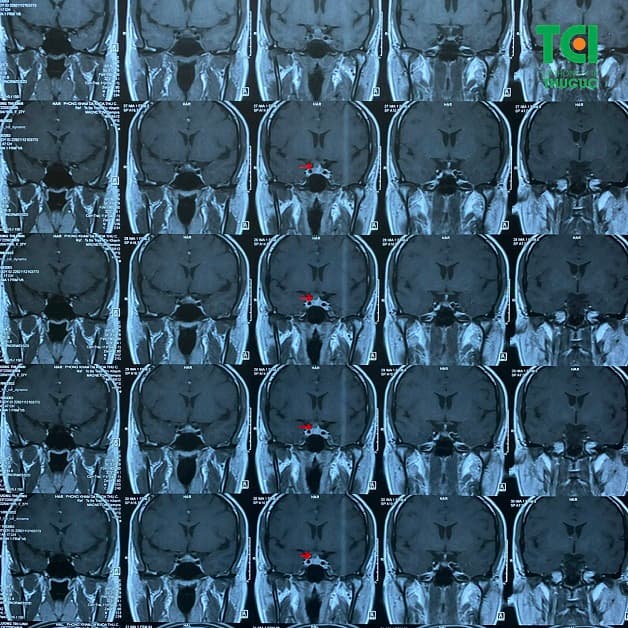

Sau khi được chỉ định thực hiện một số biện pháp chẩn đoán cận lâm sàng trong đó có chụp cộng hưởng từ MRI não (sọ não – mạch não) thì phát hiện: khối choán chỗ tuyến yên hướng tới Microadenoma tuyến yên – U tuyến yên (kích thước ~ 6x6mm, đè đẩy nhẹ giao thoa thị giác). Biến thể giải phẫu đa giác Willis. Sau tiêm thuốc đối quang từ, khối ngấm thuốc tương đối đồng nhất.

u tuyến yên gây mất ngủ kéo dài trên phim chụp MRI của bệnh nhân khám tại Thu Cúc TCI.